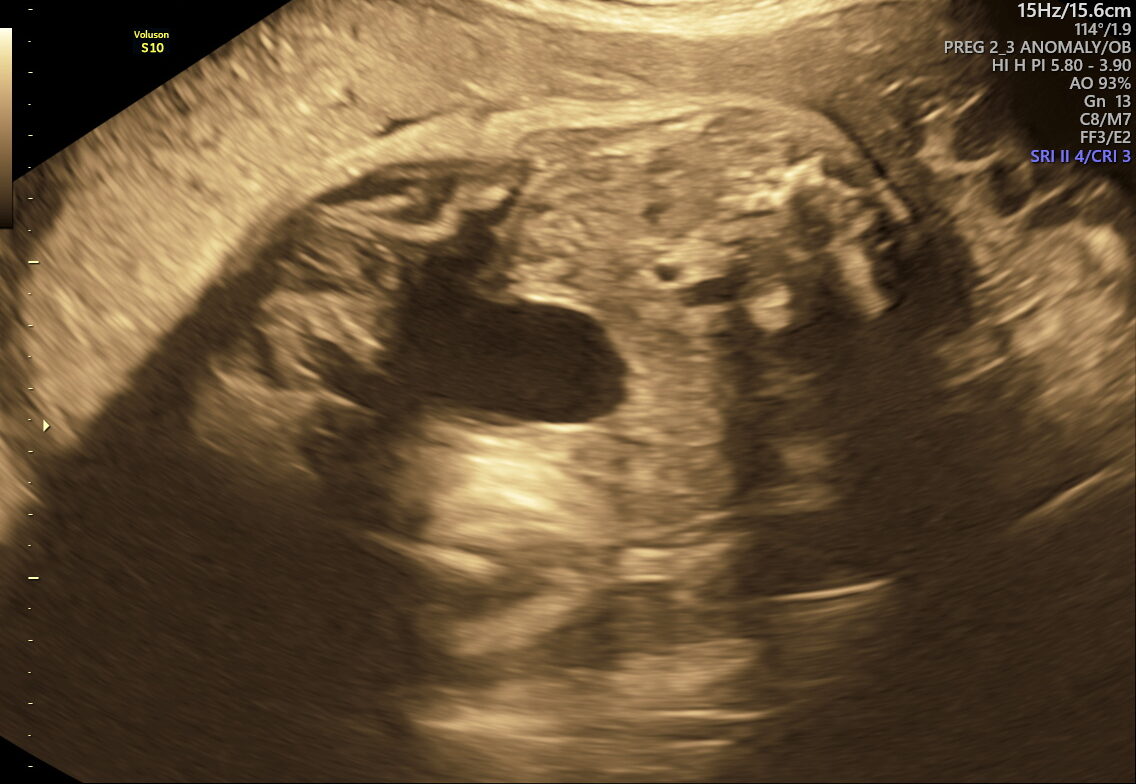

- Amniotic Fluid Levels: Detects if fluid is too low or high, which could impact delivery and baby’s health.

- Placental Health: Examines if your placenta is supplying nutrients and oxygen effectively.

This scan focuses on confirming birth readiness and spotting sudden issues that may arise close to your due date. It includes detailed Doppler studies to check blood flow in the umbilical cord and brain, ensuring your baby gets enough oxygen and nutrients.